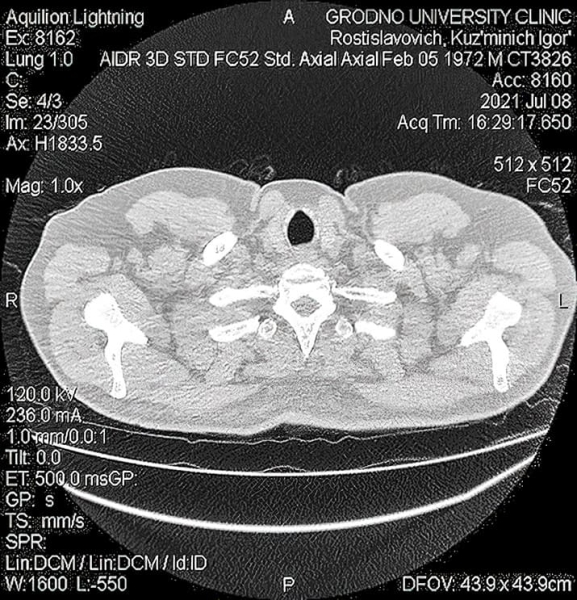

КТ органов грудной клетки: множественные консолидации в легких, отрицательная динамика в сравнении с предыдущими результатами. Воспалительные изменения по интерстициальному типу, которые с высокой степенью вероятности могут быть ассоциированы с вирусной пневмонией. Степень тяжести КТ-3.